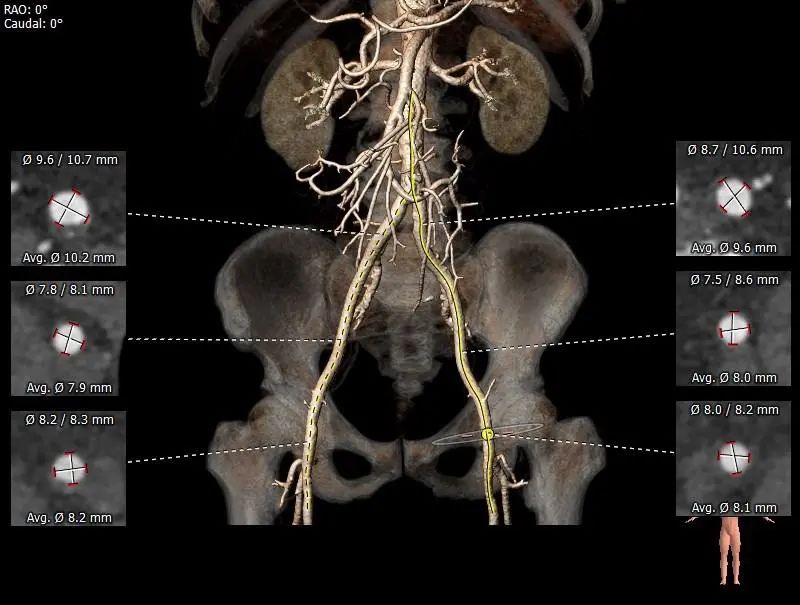

双侧髂动脉未见明显扭曲,股动脉穿刺区域未见钙化斑块,入路血管直径良好。

外周血管及主动脉弓解剖